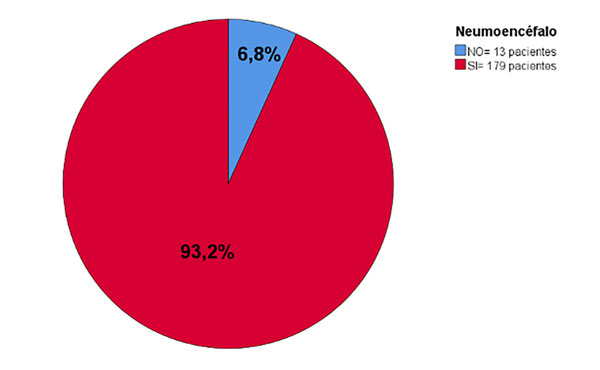

Resultados: 192 pacientes incluidos. Edad 47 ± 16.3 años, 62.5% fueron mujeres. NE 93.2%, sin NE a tensión. NE subdural (87.5%), subaracnoideo (66.6%), ventricular (15.6%). NE ˂40 años (86.4%), 40-60 (97.8%), ˃60 años (93.2%), p = 0.02. Los pacientes en edad entre los 40-60 años tienen 5.824 veces más riesgo de presentar NE que ˂40 años (OR 6.824, IC 95%; 1.395-33.380, p = 0.01). NE no se asoció con el resultado neurológico.

En la Figura 4 se muestra la prevalencia de NE. La Tabla 3 presenta la frecuencia de los patrones de neumoencéfalo y sus grados.

Figura 4. Prevalencia de neumoencéfalo postquirúrgico en cirugías de patologías de fosa posterior en posición semisentada. N = 192

Prevalencia de neumoencéfalo, neumoencéfalo a tensión, patrones y grados

En este estudio, la prevalencia de NE postquirúrgico en patología de fosa posterior en PSS fue de 93.2%, mientras que en la literatura se ha reportado una prevalencia desde 42.1% al 100%, sin embargo, rara vez se hace sintomático.